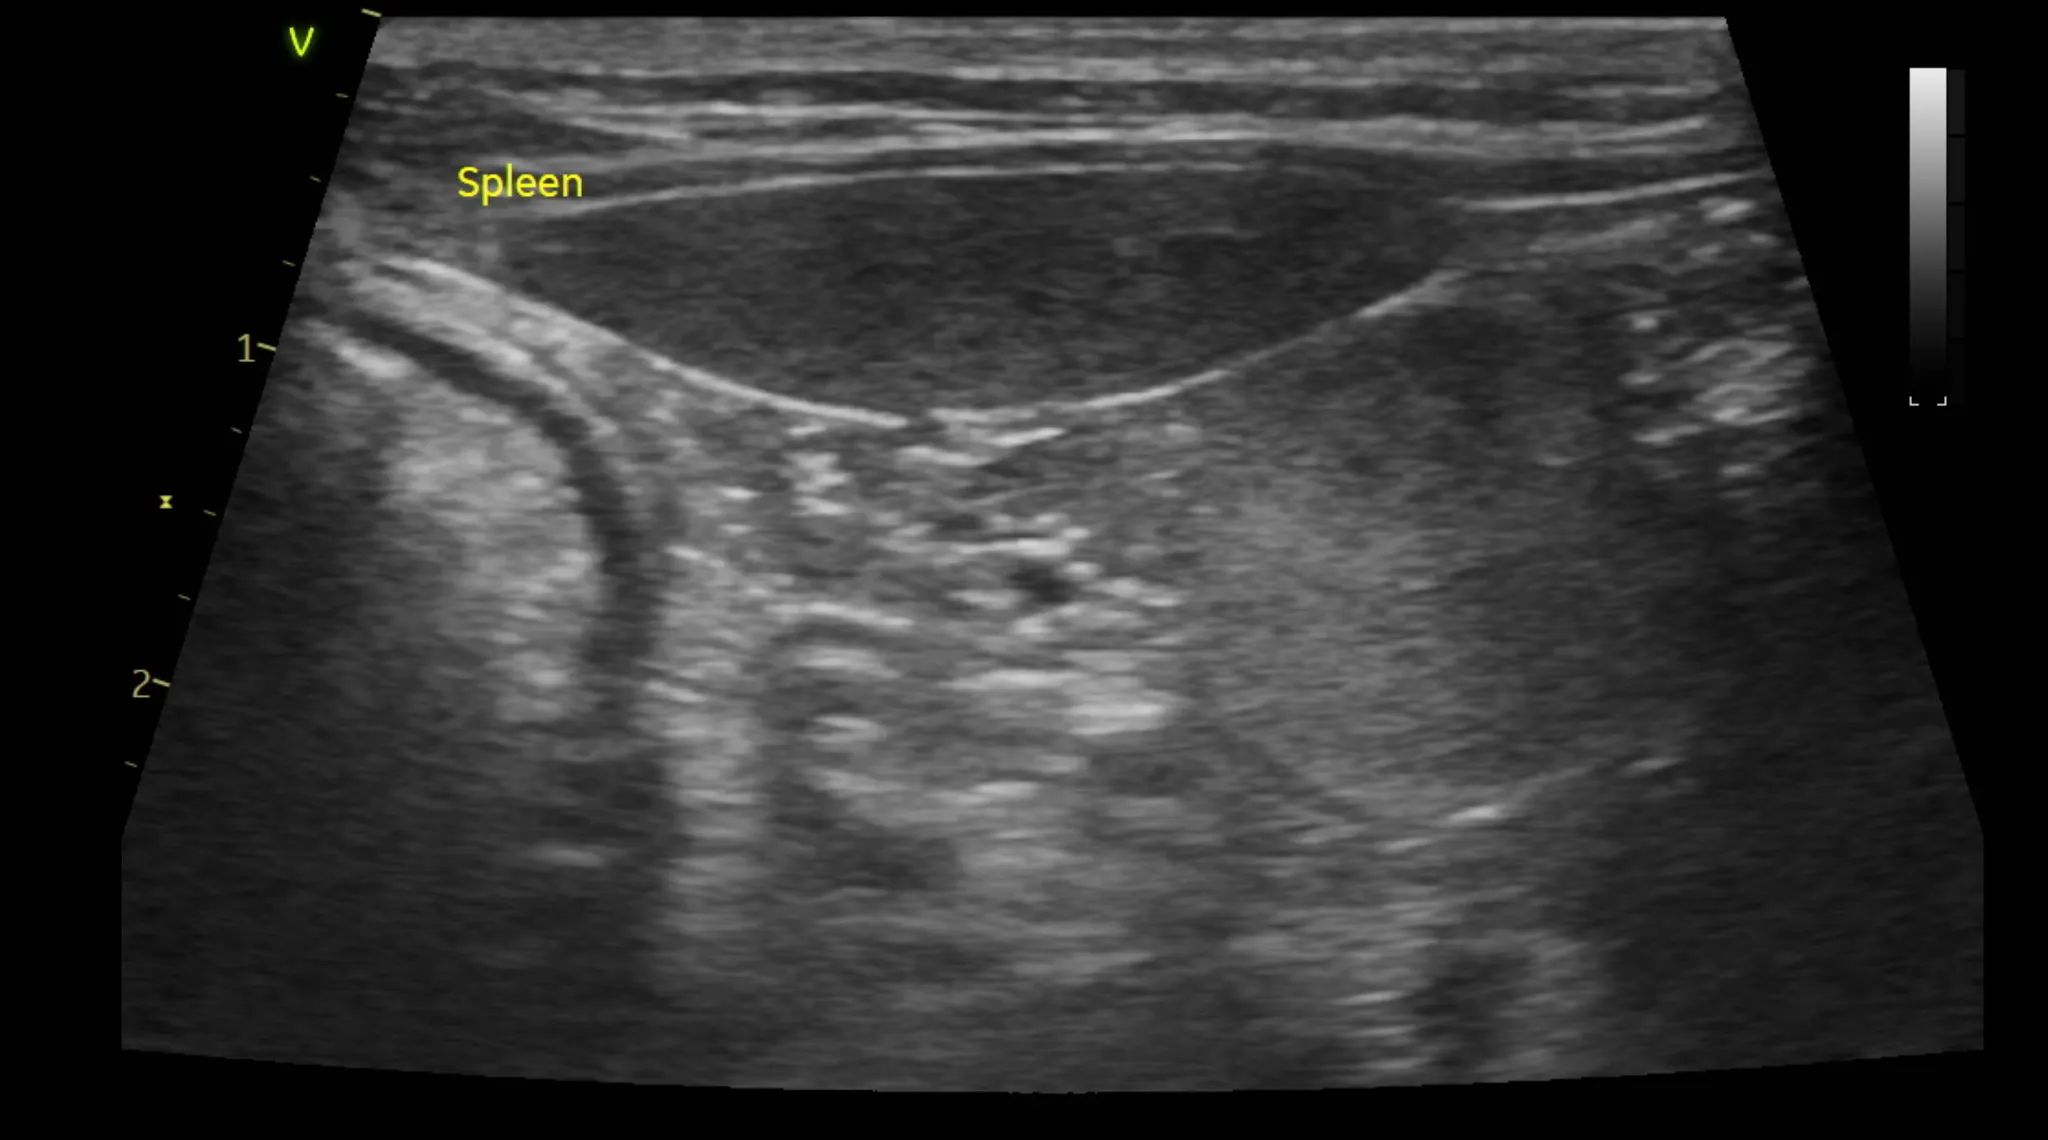

3. 복부 초음파 검사 결과

복부 초음파 검사로는 간, 신장 등 복부 장기의 모양과 결석, 종양등의 이상여부를 알 수 있습니다.

또한 방광 결석, 다낭포성 신장질환 같은 고양이에서 잘 생기는 질환의 경우 초음파 검사로만 알 수 있으므로 매우 중요한 검사 중 하나입니다.

복부 초음파 검사 상 특이사항은 발견되지 않았습니다.

1년 주기로 검사를 추천드립니다.